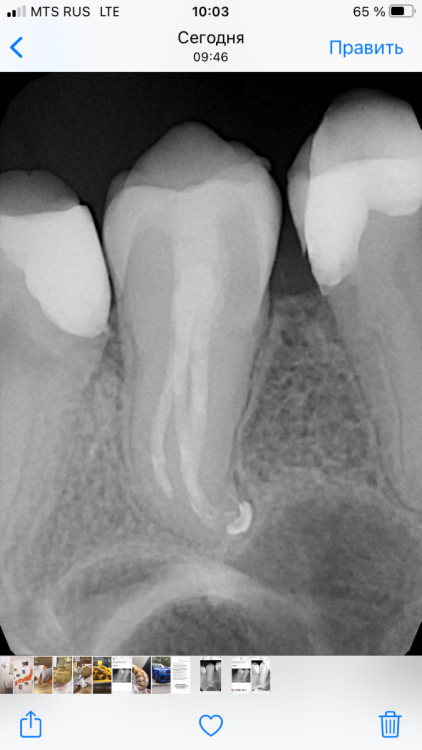

Mel17 Опубликовано 8 сентября, 2021 Поделиться Опубликовано 8 сентября, 2021 Здравствуйте! Подскажите пожалуйста, 26 зуб после эндодонтии, полтора года назад была эндодонтия, по снимку есть выход за апекс немного, но это никак не беспокоило все время, была 3 недели назад механическая трамва ( прикусила косточку на эту сторону челюсти), с тех пор как ощущаю как будто дискомфорт на этот зуб (по ощущениям как чувство распирания и отека, но визуально Отека нет). На десне появилось небольшое пятна к месту прилегание зуба к десне. Врач на Приём посмотрел, сказал на прошлом приеме до травмы 2 недели назад десна была намного Лучше... по кт и прицельному снимку признаков нет. Какие исходя из вашей практики признаки vfr и через какое время должно быть проявление на десне (одиночный карман) и рентгенологические признаки ? Спасибо... Ссылка на комментарий

Mel17 Опубликовано 14 сентября, 2021 Автор Поделиться Опубликовано 14 сентября, 2021 @dentikl подскажите пожалуйста если ли на снимке признаки трещины? Ссылка на комментарий

red_butler Опубликовано 14 сентября, 2021 Поделиться Опубликовано 14 сентября, 2021 3 минуты назад, Mel17 сказал: подскажите пожалуйста если ли на снимке признаки трещины? нет Ссылка на комментарий

Mel17 Опубликовано 14 сентября, 2021 Автор Поделиться Опубликовано 14 сентября, 2021 @red_butler Спасибо, а вот это тень так падает да, как затемнение чёрточкой ? Ссылка на комментарий

chervoncevdaniil Опубликовано 14 сентября, 2021 Поделиться Опубликовано 14 сентября, 2021 Рентгенологически трещину увидеть очень сложно,на ранних этапах чаще всего невозможно. Чаще всего когда рентген картина будет,то там и без снимка по жалобам и объективному осмотру будет ясно что она есть Ссылка на комментарий

St. Опубликовано 15 сентября, 2021 Поделиться Опубликовано 15 сентября, 2021 14.09.2021 в 10:59, Mel17 сказал: это тень так падает да, как затемнение чёрточкой ? Это так поверхности корней друг на друга накладываются. Ссылка на комментарий